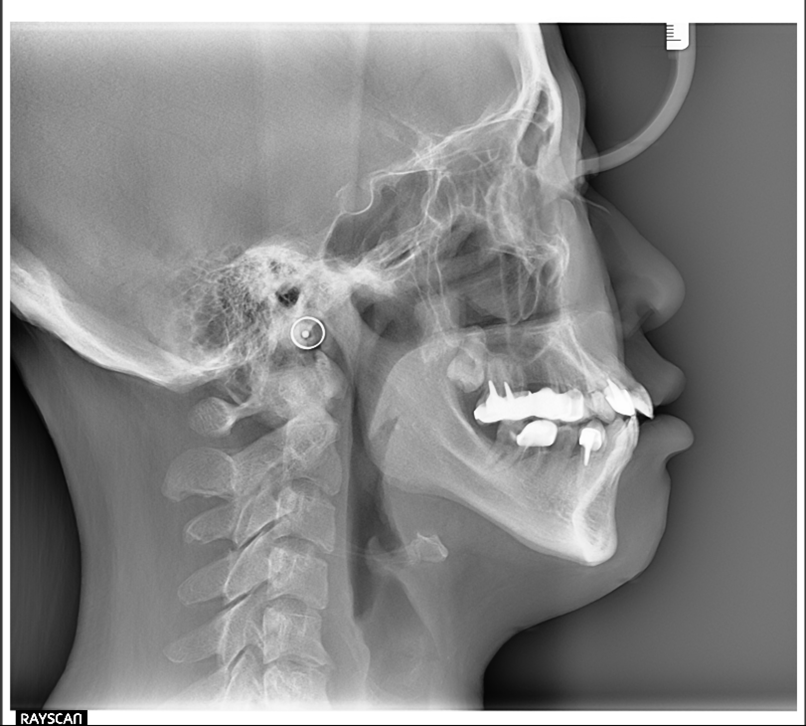

3D斷層掃描

蒔雨牙醫引進Ray scan α+,具有高解析度,低變形量,能讓我們看到更多的細節,做更全面的診斷及治療規劃,且輻射劑量低,同時兼顧安全及品質。

高解析度,連细小的根管都能看得清楚

3合1機型,可同時在診所完成電腦斷層及側顱X光片拍射,讓矯正資料蒐集更完全

可見軟硬組織清晰的影像,讓矯正醫師能更準確的分析診斷